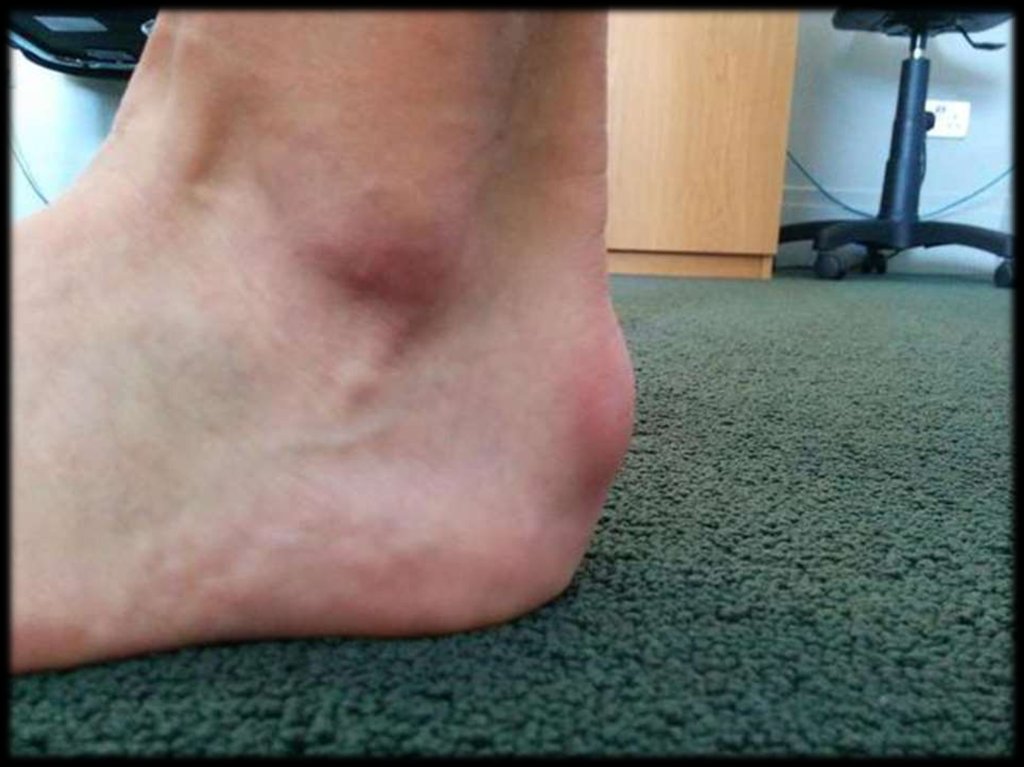

53. Подкожный бурсит ахиллового сухожилия

55.